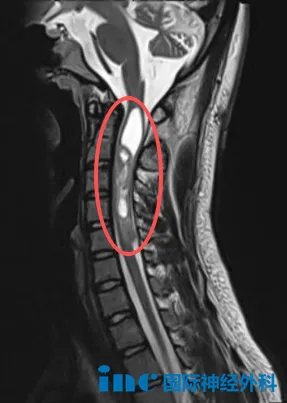

18岁男性患者帆帆,自2009年起开始艰难的求医历程。4岁时接受第一次手术,切除头顶部神经鞘瘤。14岁时确诊神经纤维瘤病2型,接受右侧小脑病损切除术。2022年10月以来,患者反复出现右下肢剧烈疼痛,严重时疼痛持续约6小时,影响睡眠;同时伴有进行性听力下降。今年7月复查显示,后颅窝、颈椎椎管及胸壁多处病灶仍有进展,右颈部病变尺寸约7.0cm×5.2cm。

咨询巴教授后,他们了解到需要分次手术处理多处病灶。鉴于颈髓病灶持续进展可能导致瘫痪风险,首次手术将优先处理该部位。通过面对面交流,教授的回复给予他们极大信心,并提供决策勇气。